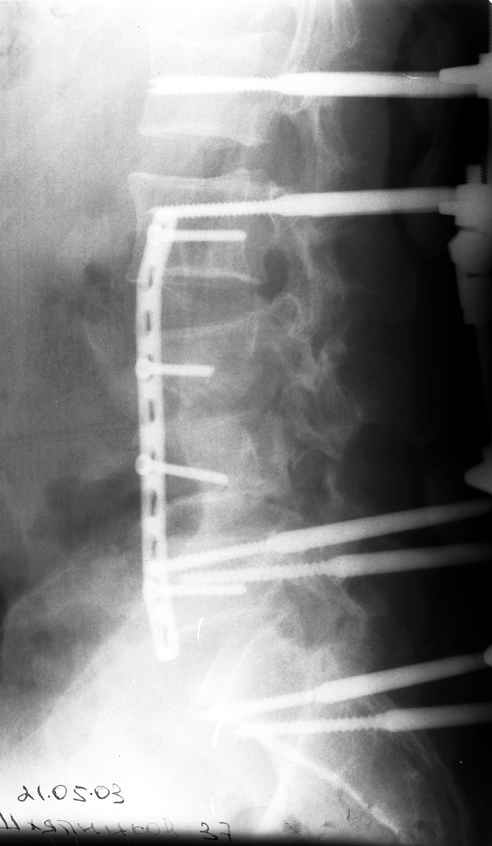

Первым этапом наложен наружный транспедикулярный аппарат, грубая деформация позвоночника устранена. Затем пациент перевёрнут на бок и выполнен забрюшинный доступ по Чаклину. При ревизии обнаружены дислоцированные позвонки "внедрившиеся" в m. psoas. Что интересно, передняя продольная связка хотя и была натянута как струна и отслоена от тел смежных позвонков, но не разорвалась. Ревизия позвоночного канала обнаружила достаточное жизненное пространство для дурального мешка вследствии произошедшей травматической ламинэктомии. Задние отделы повреждённых сегментов переломаны в "крошку". Диск L2-l3 был повреждён поэтому выполнен спондилодез L2-L5. При этом тела 4-го и остатки тела 3-го позвонков использованы в качестве костнопластического метерьяла. Тело 4-го позвонка вертикально и использовано для замещения дефектов на уровне сегментов L3,L4. Для фиксации отломков использована пластина. Стабилность позвоночника обеспечивается АВФ. Неврологическая симптоматика в послеоперационном периоде практически не изменилась. Получает комплексное лечение, планируется в скором времени его вертикализация.